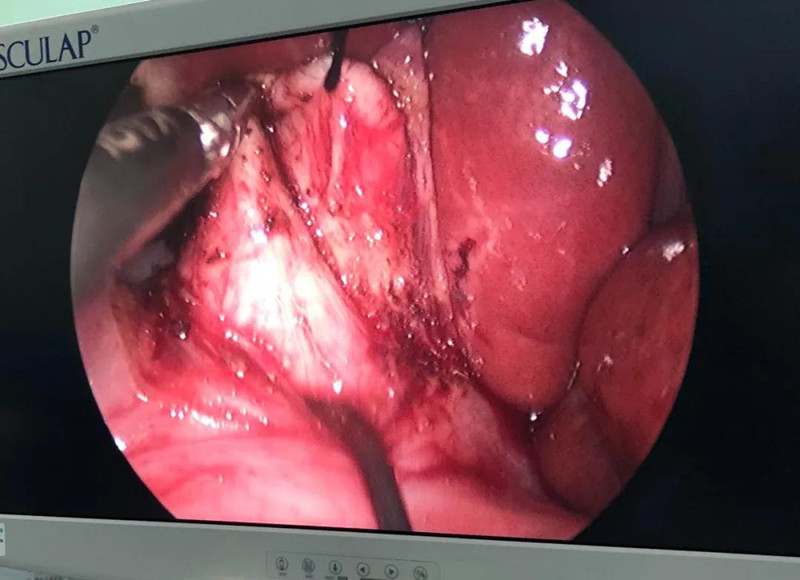

最难:防止门静脉出血

崔钊主任说,术前大家最担心的是门静脉出血,因为它比动脉出血更凶险,可危及生命。“馨馨来院时已经出现炎症,周围粘连严重。而静脉左侧临着肝总动脉,下边连着十二指肠乳头、胰腺,它和背侧的门静脉紧贴着,一不小心,就会导致门静脉出血。”

为了规避出血风险,术前,团队备足了血,又配备一名助手,一旦术中门静脉出血,马上开腹止血。另外,还有肝脏动脉变异的可能,幸好,术中这些个担心都没有出现。